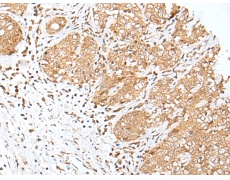

IHC positive control: |

Human gastric cancer and human esophagus cancer |

IHC Recommend dilution: |

25-100 |